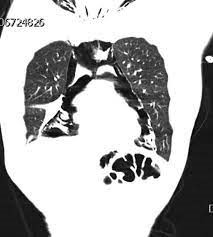

病人 1:30多岁女病人,没有过去史。一天, 换了一个新的避孕药。第二天开始呕吐,一天吐了25次。来到急诊室。查了一大堆,包括胸部CT。 CT发现纵隔充满空气。这叫气纵隔(Pneumomediastinum)。

图来自Google。和这个病人的气纵隔类似,纵隔大量气体。